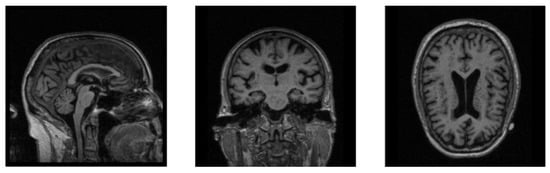

In Figure 3, we show the data changes before and after data denoising. Through data denoising, the noise regions in the raw 3D image are cut out, and the size of the data input into the neural network can be reduced from 192 × 192 × 160 to 160 × 160 × 120. Because the noise data is reduced, the neural network model can better extract useful features for diagnosis. In addition, data denoising helps to reduce calculation by decreasing parameters of the fully connected layer in our diagnosis network.

Figure 3.

Raw image and the denoised image. The three views of the raw image are shown in (a), and (b) is the corresponding denoised views.

We use the AD-image group and the NC-image group to explain our data denoising process. First, we obtain their mean images and according to Equation (1). Then the difference image is calculated according to Equation (2). By normalization, we can get the difference image with the voxel values between 0 and 1. Next we transform into its corresponding mask according to a given threshold . Finally, each AD-sample image and each NC-sample image are cropped according to the mask to achieve noise reduction. In this way, the lesion areas corresponding to large differences in an image will be preserved, and the useless voxels can be cut off. In Figure 3, we show the views of a raw image at three dimensions and their corresponding denoised views. It can be found that the useless information near the boundaries is reduced, but the main information is not lost. The implementation details of data denoising are shown in Algorithm 1.